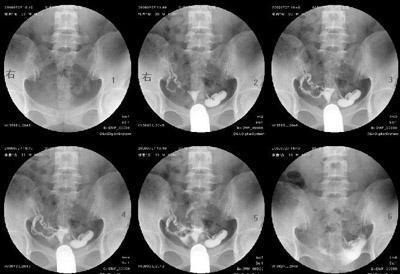

做输卵管造影是检查输卵管堵塞常用的一种检查方法,输卵管造影的准确率高,对于输卵管堵塞能够作出正确的诊断,所以,输卵管造影是重要的检查方法,很多的女性对于输卵管造影后,要注意些什么不是很清楚,我们来详细了解一下: